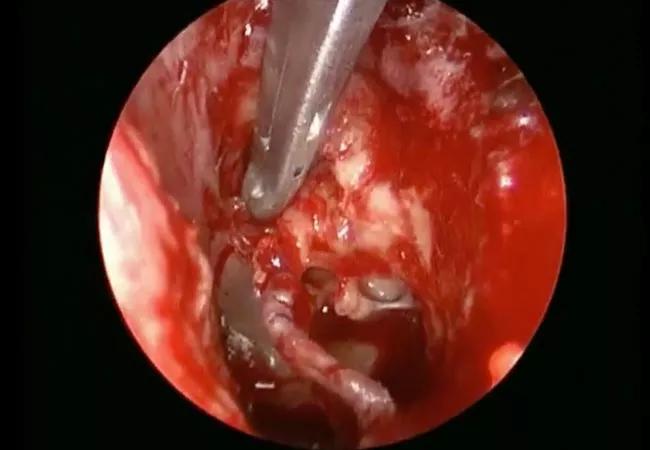

In another case illustration, a surgical endoscope was used to remove a locally advanced cholesteatoma. Because of the increased visualization of the 30-degree endoscope (see video below), we were able to eradicate the cholesteatoma without sacrificing the ossicles. Techniques like this stand to improve hearing and control rates of cholesteatomas for chronic ear disease patients.

Surgical endoscope to remove a locally advanced cholesteatoma